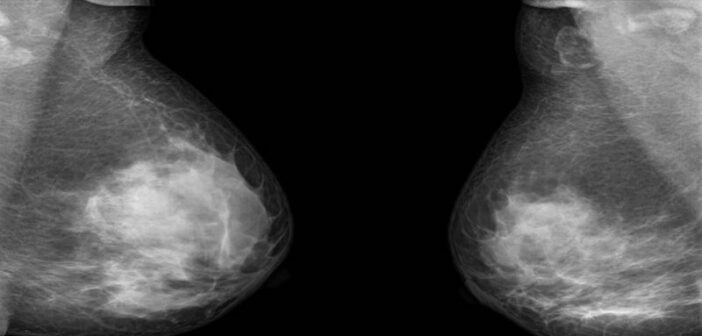

Mammograms are a safe, effective way to detect the presence of breast cancer in women. But doctors recommend most females should start getting mammograms after the age of 40 in part because the procedure involves small doses of ionising radiation.

While that is not as accurate as a mammogram (a mammogram can be 80% to 98% effective in detecting breast cancer in older women with non-dense breast tissue), it does add an additional diagnostic tool for younger women and women with dense breast tissue who are otherwise advised not to get a mammogram because of their age or breast density.

Because this method uses low-voltage electricity instead of radiation like a mammogram, Sanchez-Terrones says it can be used repeatedly on women of any age. It therefore is designed to be used in conjunction with a mammogram to provide an even more accurate overall diagnosis.